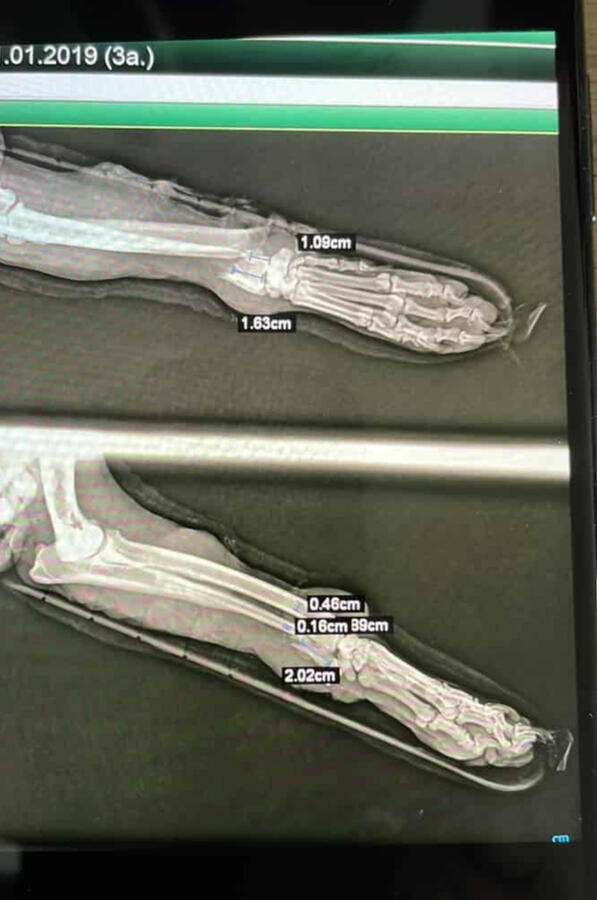

In addition, I continuously train in the areas of orthopedics, traumatology, and pain control. General and traumatological surgery.